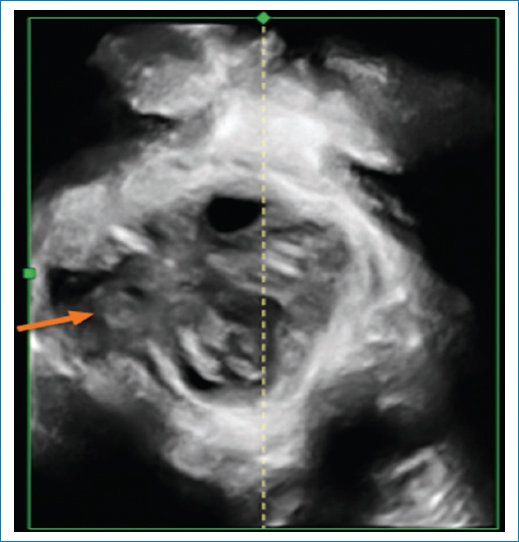

• – Evaluación del esfínter anal: para valorar el esfínter anal se deben realizar dos movimientos, a partir del plano mediosagital, un giro de 90 grados y una inclinación de la sonda hacia el canal anal, obteniendo una imagen axial del esfínter anal2. Se debe realizar su inspección en 3D y 4D con cortes tomográficos multicorte donde se pueden detectar lesiones del esfínter anal. La ecografía endoanal sigue siendo de elección, sin embargo la ecografía transperineal puede detectar lesiones, hipertrofia del esfínter anal interno en fisuras crónicas y fistula anal (Fig. 16).

Figura 16. (A) Cortes axiales donde se observa una cicatriz del esfínter anal interno. (B) Untrasonido tomográfico transperineal donde se observa una lesión del esfínter anal interno.